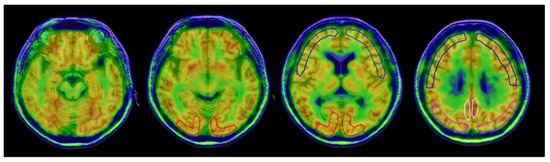

2.4. Image Analysis

- Okazawa, H.; Ikawa, M.; Jung, M.; Maruyama, R.; Tsujikawa, T.; Mori, T.; Rahman, M.G.M.; Makino, A.; Kiyono, Y.; Kosaka, H. Multimodal analysis using [11C]PiB-PET/MRI for functional evaluation of patients with Alzheimer’s disease. EJNMMI Res. 2020, 10, 30. [Google Scholar] [CrossRef]